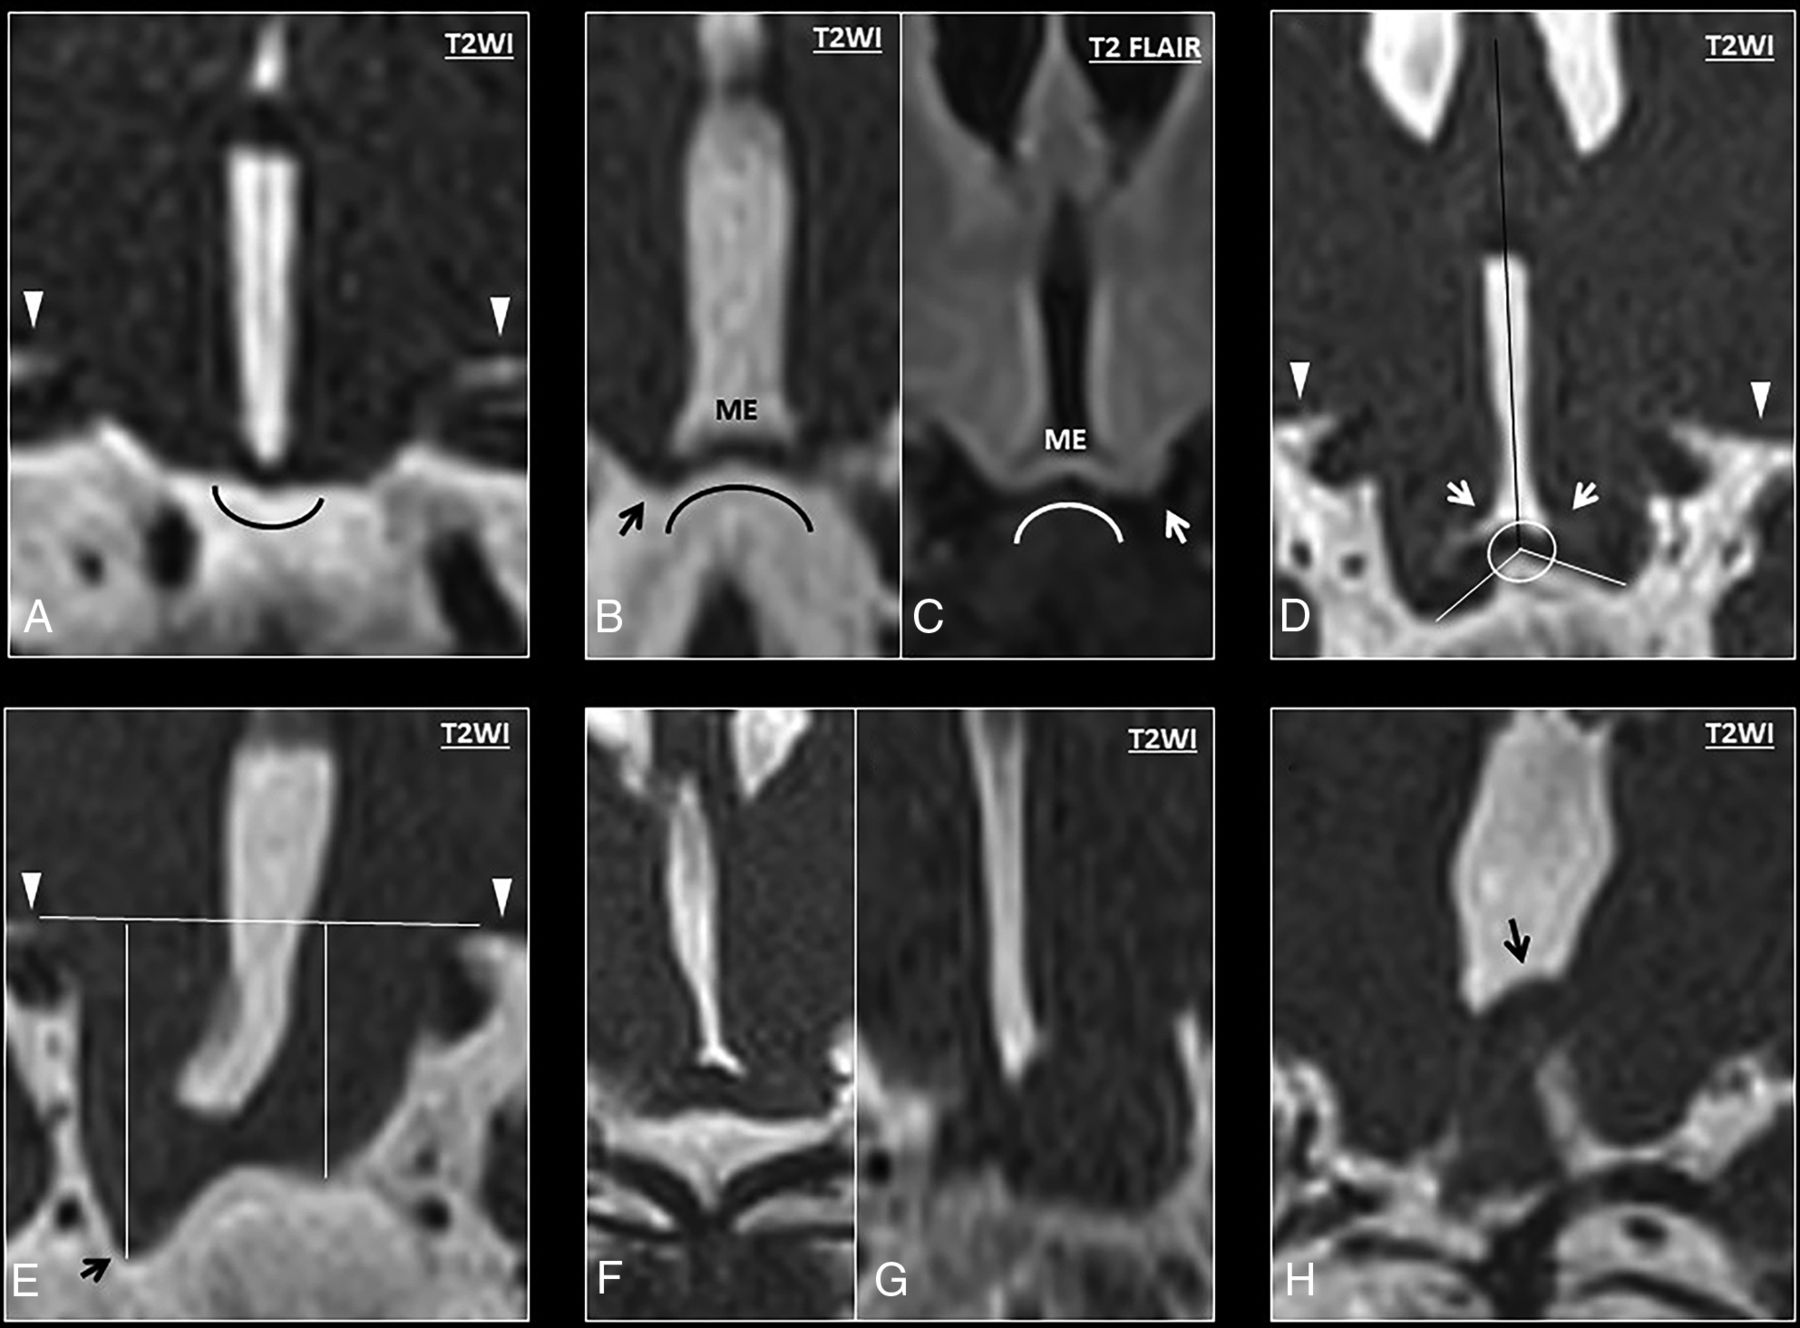

Axial T2 morphology.

Morphology of the ventromedial hypothalamus was assessed at the level of the optic radiations. While none of the controls showed hypothalamic overfolding (Fig 2A), 7 patients with DFNX2 demonstrated a folded appearance of the ventromedial hypothalamus (P < .001). This hypothalamic overfolding was characterized by an abnormal external or internal cleft in the ventromedial hypothalamus in 7 patients; most (n = 6) showed bilateral abnormal clefts on axial images rather than unilateral ones (Fig 2B–G). All 7 patients showed external clefts compared with internal clefts (pointing toward the third ventricle), which were only present in 5 patients with DFNX2. None of the controls (67 patients) showed hypothalamic clefts (P < .001), and 2 controls had suboptimal axial images. The κ index ranged between 0.76 and 0.95.

A, Axial T2 image of a normal hypothalamus at the level of the optic radiations. B–G, Axial T2 images of the hypothalamus in a patient with DFNX2, which demonstrate progressive folding of the ventromedial hypothalamus. Note the presence of bilateral clefts in most cases, with external clefts being more easily recognizable (arrows). Internal clefts are also noted on B and C (arrowheads).

On axial T2 images.

The folded appearance of the ventromedial hypothalamus (sensitivity [SE], 100%; specificity [SP], 95.8%) characterized by an abnormal internal/external cleft (SE 100% SP 95.7%) showed high specificity and sensitivity as well as interobserver agreement for patients with DFNX2 (Fig 2).